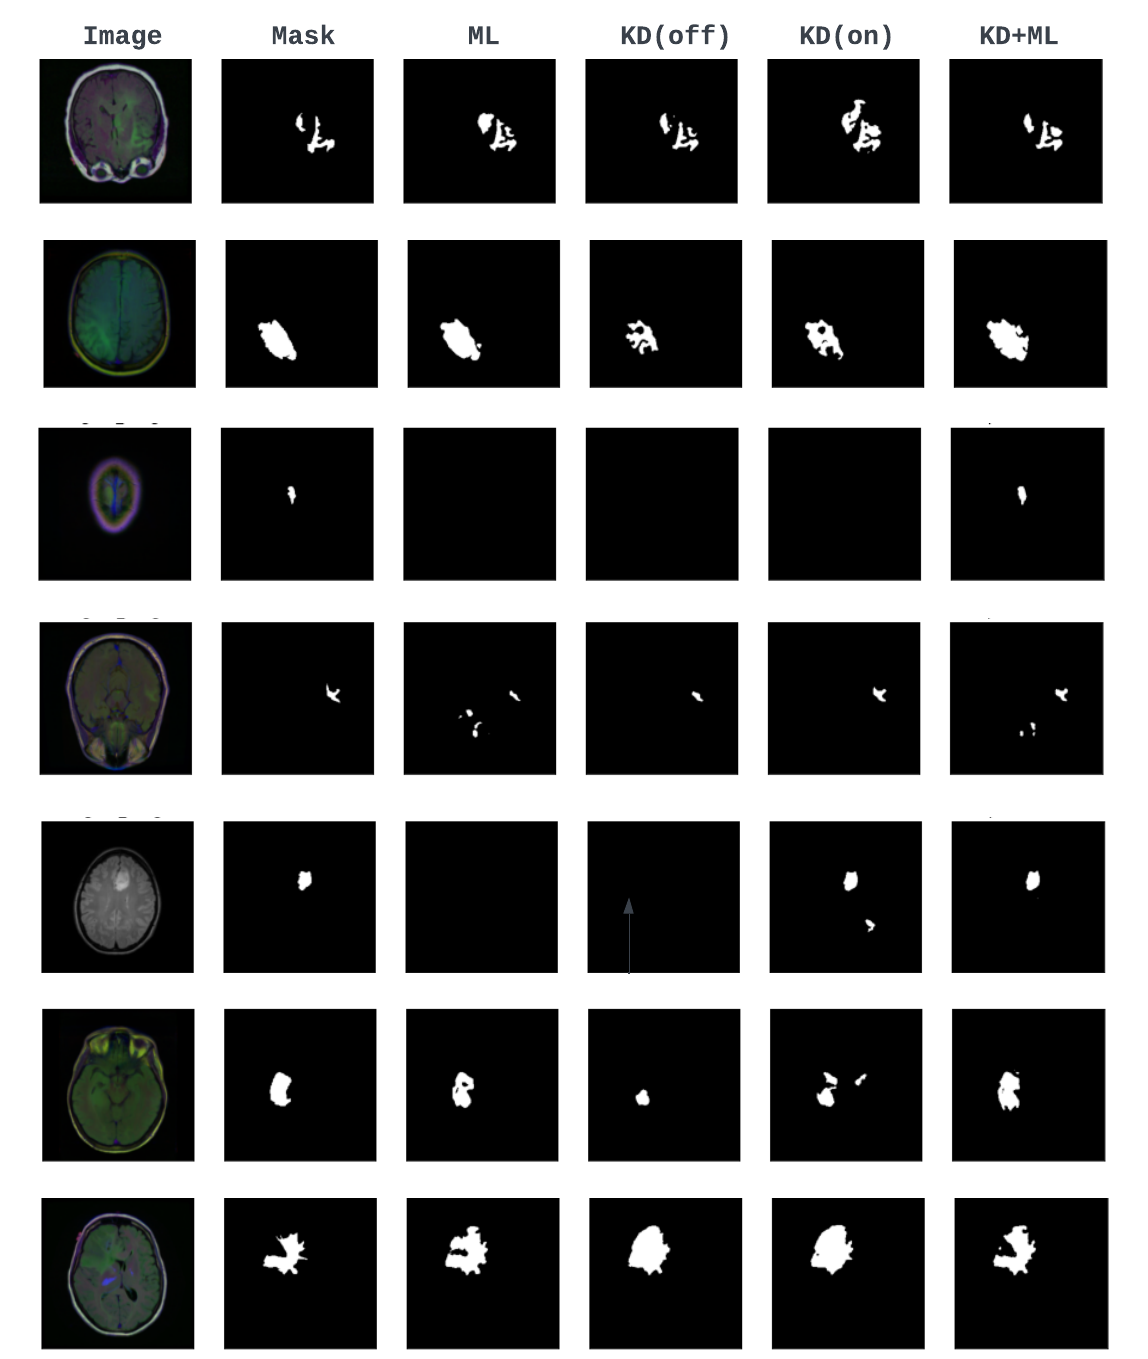

5.2 Segmentation Task

The corresponding results of U-Net with ResNet50-ResNet18 network architectures for the segmentation task are reported in Table 4. These results depict similar trends observed for the classification task, further emphasizing the importance of combining KD with ML and the influence of knowledge diversification. Moreover, it establishes the generalizability of the proposed approach to more than one type of task.

To better appreciate the significance of the proposed approach, we provide a qualitative comparison of different distillation techniques and information-sharing strategies using individual student predictions for some hard-to-segment test samples. Figure 4 extensively compares all the models for three test samples. In general, it can be observed that KD-only and ML-only models struggle with the segmentation of small regions of interest. It can also be noticed that for conventional models, only one of the two students manages to predict these small regions. In our proposed approach, an ensemble of student predictions is used for the final predictions, facilitating the student networks to consistently predict the region of interest and yield optimal performance. Moreover, student networks trained using a diverse knowledge paradigm demonstrate a superior ability to discern finer structures compared to other models.

We demonstrate the importance of combining KD with ML by comparing all models trained with a knowledge diversification paradigm in Figure 5. It can be noticed that the combined KD + ML model successfully detects these small regions of interest from these hard sample images where KD-only and ML-only models fail. Similarly, to underscore the significance of knowledge diversification over other learning strategies, we show sample predictions from the combined KD + ML model trained with V1 (predictions only), V2 (features only), and a diverse knowledge paradigm, V3 (both predictions and features) (Figure 9 in the supplementary material) where we observe that the V3 strategy helps detect small and fine regions of interest better than V1 and V2.

5.4 Explainability

To understand the effect of using different learning styles for the classification task, we used the popular Centered Kernel Alignment (CKA) metric [27] to measure and compare the similarity of learned representations of different layers of the teacher and student networks. As highlighted (blue box) in Figure 6, the CKA plots show increased similarity between the higher layers of the teacher and final layers of the student networks for the knowledge diversification paradigm (V3). As the deeper layers of a network are considered task-specific, this increased similarity could potentially explain the improved performance of KD + ML with V3 compared to all other knowledge distillation and sharing strategies (Figure 10 and 11 in the supplementary material). Finally, Figure 7 shows the ensemble segmentation masks of different knowledge-sharing models trained with the knowledge diversification paradigm (V3).